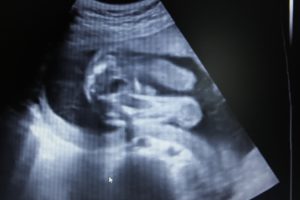

УЗИ, проведенное на 21 неделе беременности, позволяет определить пол будущего малыша, увидеть внутренние органы.

Специалист ультразвуковой диагностики оценит вероятность развития патологий, определит частоту биения сердца ребенка и состояние амниотической жидкости, установит степень двигательной активности, проведет измерения матки и плода.

При желании будущая мама сможет сама все увидеть, если УЗИ проведут в 3Д или 4Д формате, и сделать первую фотографию ребенка.

Ультразвуковое исследование на 21-й неделе беременности позволяет детально осмотреть плод, оценить его развитие, определить пол, а также проверить обвитие пуповиной, состояние плаценты, уровень околоплодных вод и матки. Кровоток в сосудах матки и плаценты анализируется с помощью допплерографии. Процедура безопасна, безболезненна и важна для специалистов.

На 21-й неделе беременности при ультразвуковом исследовании пол ребенка становится ясным. У девочек половые органы представлены двумя параллельными линиями, у мальчиков — небольшим копьевидным выступом.

На 21-й неделе беременности органы и системы плода сформированы, постепенно увеличиваются в размерах, начинают выполнять свою функцию. Головной мозг функционирует активнее – малыш улыбается, хмурится, совершает хватательные движения ручками, перебирает ножками.

- улыбается или хмурится (особенно хорошо это видно, если исследование проводится в формате 3D или 4D);

- сосет пальцы;

- сгибает-разгибает ножки и ручки (координация движений пока отсутствует);

- хватается ручками за пуповину;

- различает звуки (малыш по-разному реагирует на голоса и шумы, при раздражающих резких звуках может начать хаотичное испуганное движение конечностями).